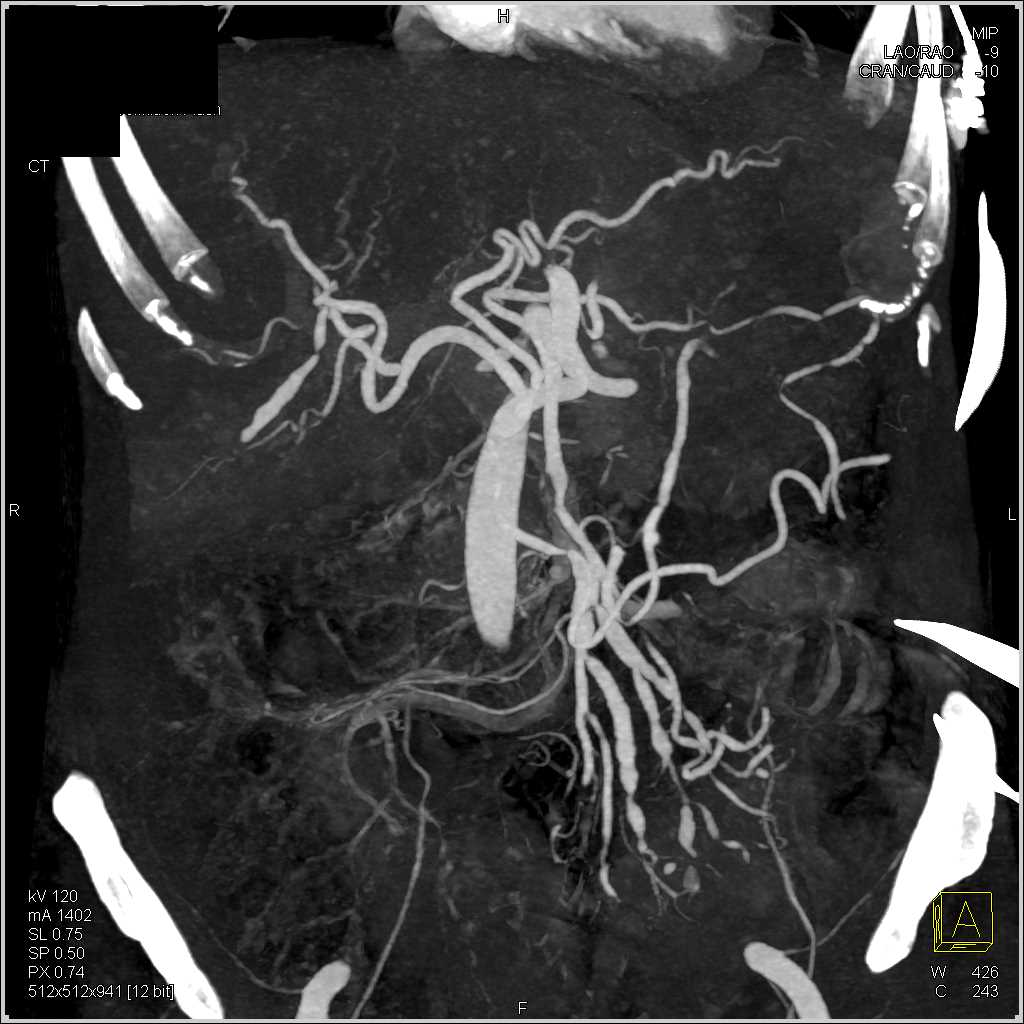

SMA Encasement by Carcinoid Tumor